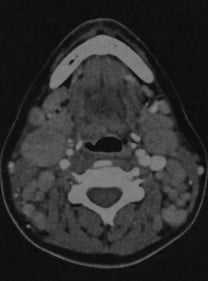

Лимфома шеи у женщины с хроническим лимфолейкозом. КТ с контрастированием: выраженное увеличение размеров и количества шейных лимфатических узлов, особенно в переднем и боковом треугольниках шеи. Плотность лимфатических узлов соответствует окружающим мышцам или выше.